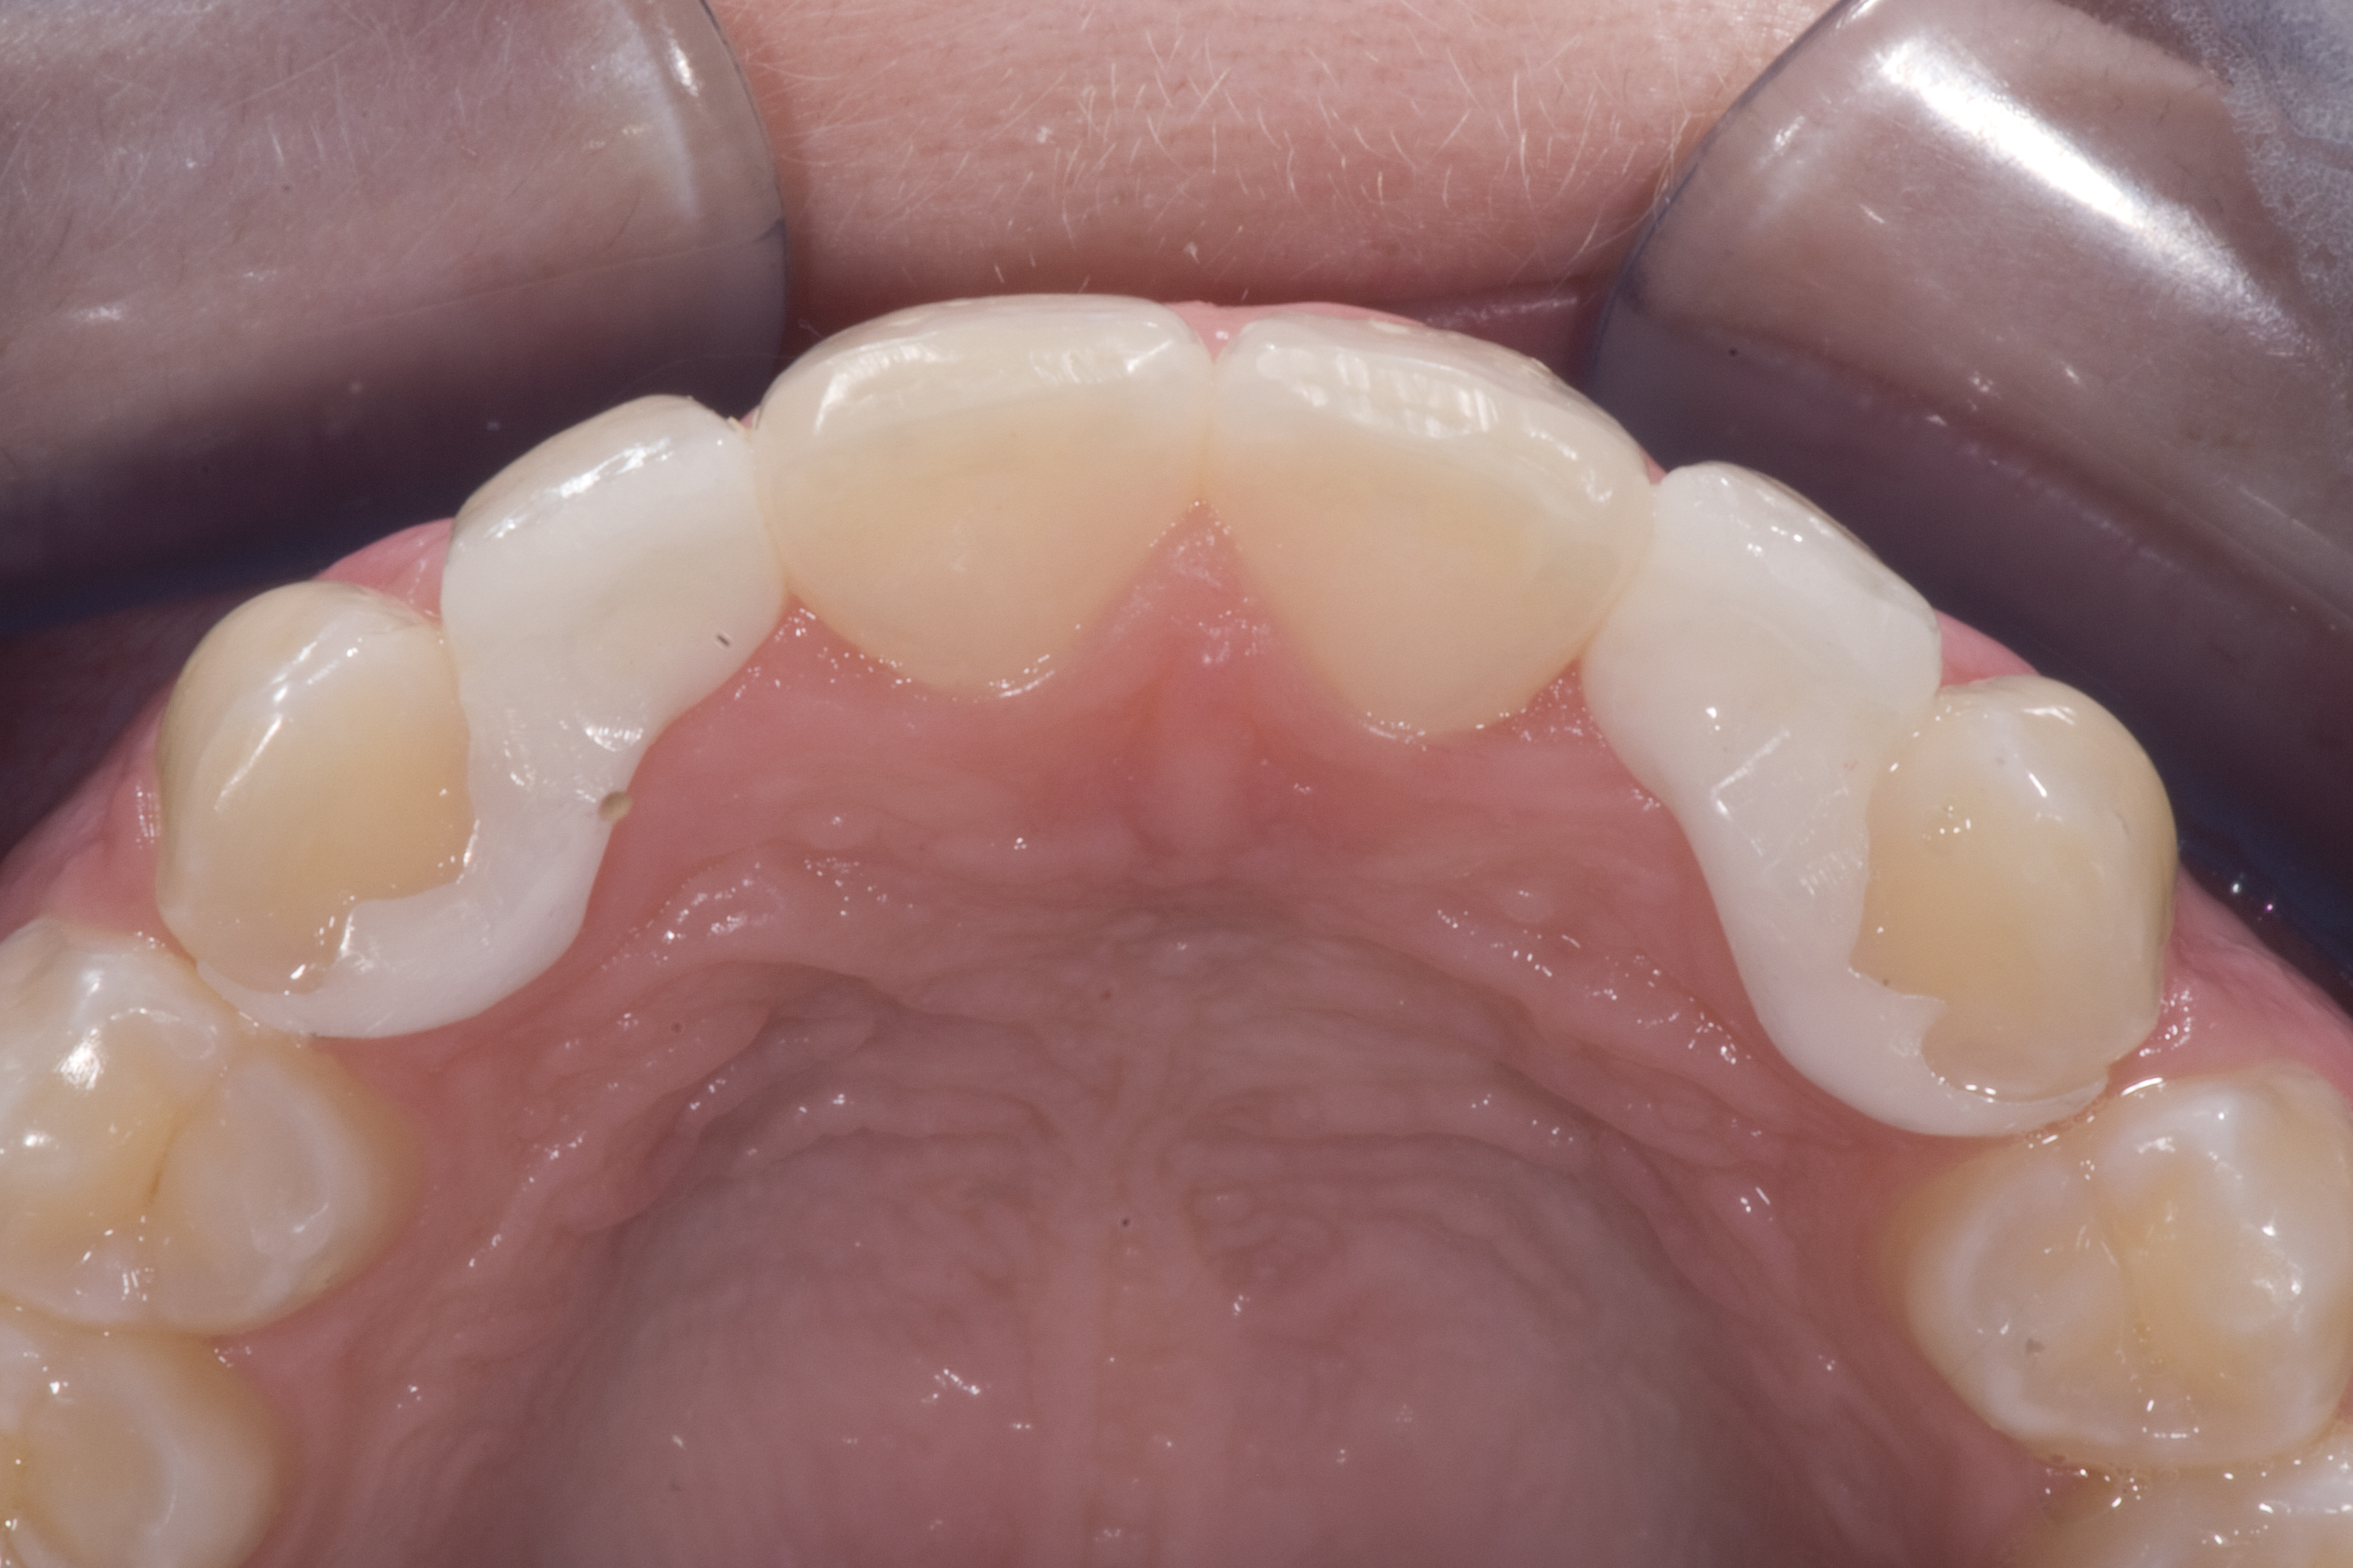

(5.) Double-wing metal resin-bonded bridge replacing lateral incisor (lingual view).

Figure 5

A 14-year-old patient presented to the office with his mother (Figure 1). His chief complaint involved the large spaces between the teeth created by his missing right maxillary lateral incisor and his small left maxillary lateral incisor. He desired to replace the missing tooth with an implant and create a beautiful smile. Upon examination, he was found to have a class I canine and molar relationship, but because he had a tooth size/arch size discrepancy and space distal to the right central incisor, the remaining incisors had drifted to the right. The left maxillary lateral incisor was peg-shaped and in a cross bite position. Studies have shown a clear association between congenitally missing teeth and reduced tooth size.59-62 Because he was only 14-years-old at the time and could not have implants placed until the cessation of growth (somewhere in the vicinity of 22 years old), he was sent to the orthodontist for alignment of the teeth.16,17 After 2 years of orthodontics, the appliances were removed, and his tooth coloration was improved using carbamide peroxide bleaching (Figure 2). Because some form of provisional needed to be placed until he was finished growing, a double-wing metal resin-bonded bridge was chosen. As discussed earlier, this is the ideal transitional prosthesis for patients that have congenitally missing maxillary lateral incisors. The benefits of this type of prosthesis include its ability to be removed and rebonded during the surgical phase of treatment and its ability to retain the roots in their proper position after orthodontic treatment.16 The final plan for the patient was to increase the width of the central and the maxillary left lateral incisor, utilizing porcelain laminate veneers to achieve the appropriate width/length ratio of 80%. A wax-up was created to idealize tooth size, a putty matrix was made from the wax-up to facilitate bonding of the incisors, and a non-precious, double-wing metal resin-bonded bridge was fabricated for lateral incisor replacement. Once the teeth were bonded to ideal size, the “Maryland Bridge” was fabricated from a polyvinyl arch impression with the newly bonded teeth (Figure 3). The metal frame was cast from a non-precious alloy to allow for fabrication of a very thin frame and to create a better surface for bonding. After sandblasting the internal aspect of the frame with CoJet™ silica (3M ESPE), accomplishing salinization, and executing cementation with a dual-cure resin cement, a fairly good adhesion to the frame was anticipated.29 The enamel surface was etched with phosphoric acid for 30 seconds, the primer (Single Bond Plus, 3M ESPE) was applied to both the internal surface of the sandblasted framework and the etched enamel, and the bridge was cemented with RelyX™ ARC (3M Espe) dual-cured resin cement (Figure 4 and Figure 5).